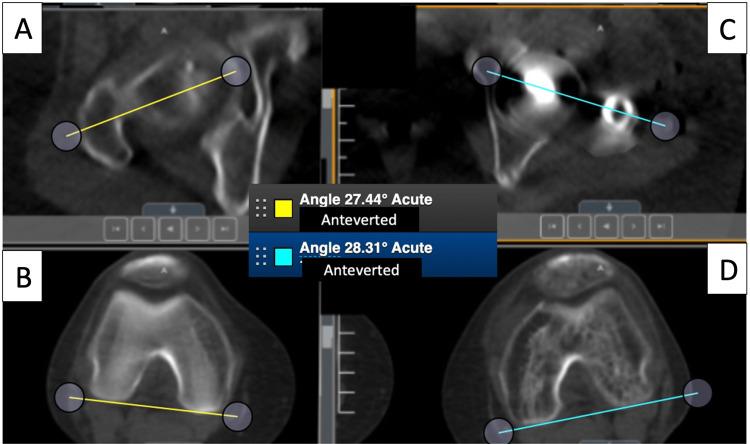

An institutional review board (IRB) approved prospective study that was performed at a U.S. level 1 trauma center. After IM nailing of comminuted femur fractures, a computed tomography (CT) scanogram was routinely performed to detect the difference in the postoperative femoral version. Patients with malalignment greater than 15 degrees compared to the contralateral side were informed about the discrepancy and offered to have it acutely corrected. A four-pin technique was used: two Schanz pins were used for measuring angles and two different pins were used to turn and correct the malalignment. The pin in the distal fragment is placed directly under the nail to prevent shortening in comminuted fractures. The nail was unlocked either proximally for retrograde nails or distally for antegrade nails. The Bonesetter Angle application was used as a digital protractor to intraoperatively measure the two reference pins and correct the malrotation. Alternate holes were used for relocking the nail. All patients received a CT scanogram after correction.

19/128 patients with comminuted femoral fractures over five years with malrotations between 18 and 47 degrees were included in the study with an average malrotation of 24.7 + 8 degrees. All patients were corrected to an average of 4.0 +/- 2.1 degrees difference, as compared to the contralateral side (range 0-8). No patients required further surgeries to correct malrotation.